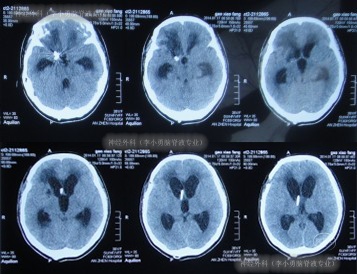

患者于2013年11月4日,突发剧烈头痛,难以忍受,前往北京某三甲医院进行头颅CT示蛛网膜下腔出血(图-1),随即进行头颅CTA检查确诊为右前交通动脉瘤(图-2)。

图-1:2013年11月4日

术后第4天即腰大池引流4天后复查头颅CT示右侧基底节区斑片状低密度影,和因腰大池引流脑室较前变小(图-3)。

图-3:术后4天头颅CT